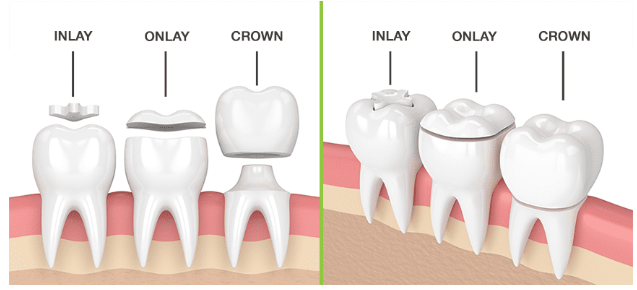

INLAY ONLAY CROWNS

INLAY ONLAY CROWNS